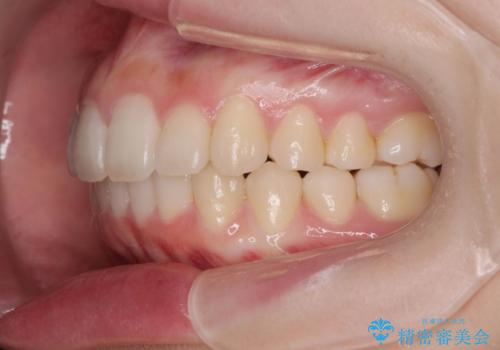

サクソフォン(アルト)の演奏で崩れてしまった歯並び、マウスピース矯正治療

- 高校時代の吹奏楽の部活でサクソフォン(アルト)を担当、「一生懸命練習をしすぎて気づいたら歯並びが悪くなっていた。矯正治療を受けたい!。」

とマウスピース矯正を希望され来院されました。

口腔内の清掃状態の良さに加えて、マウスピースを毎日きっちりと装着し、しっかりと使用していただけたことからワイヤー矯正は行わずにきれいに歯並びを治すことができました。

途中顎位が変わり、マイクロインプラントを併用した上顎臼歯の遠心移動が必要となったため治療が長期化しました。